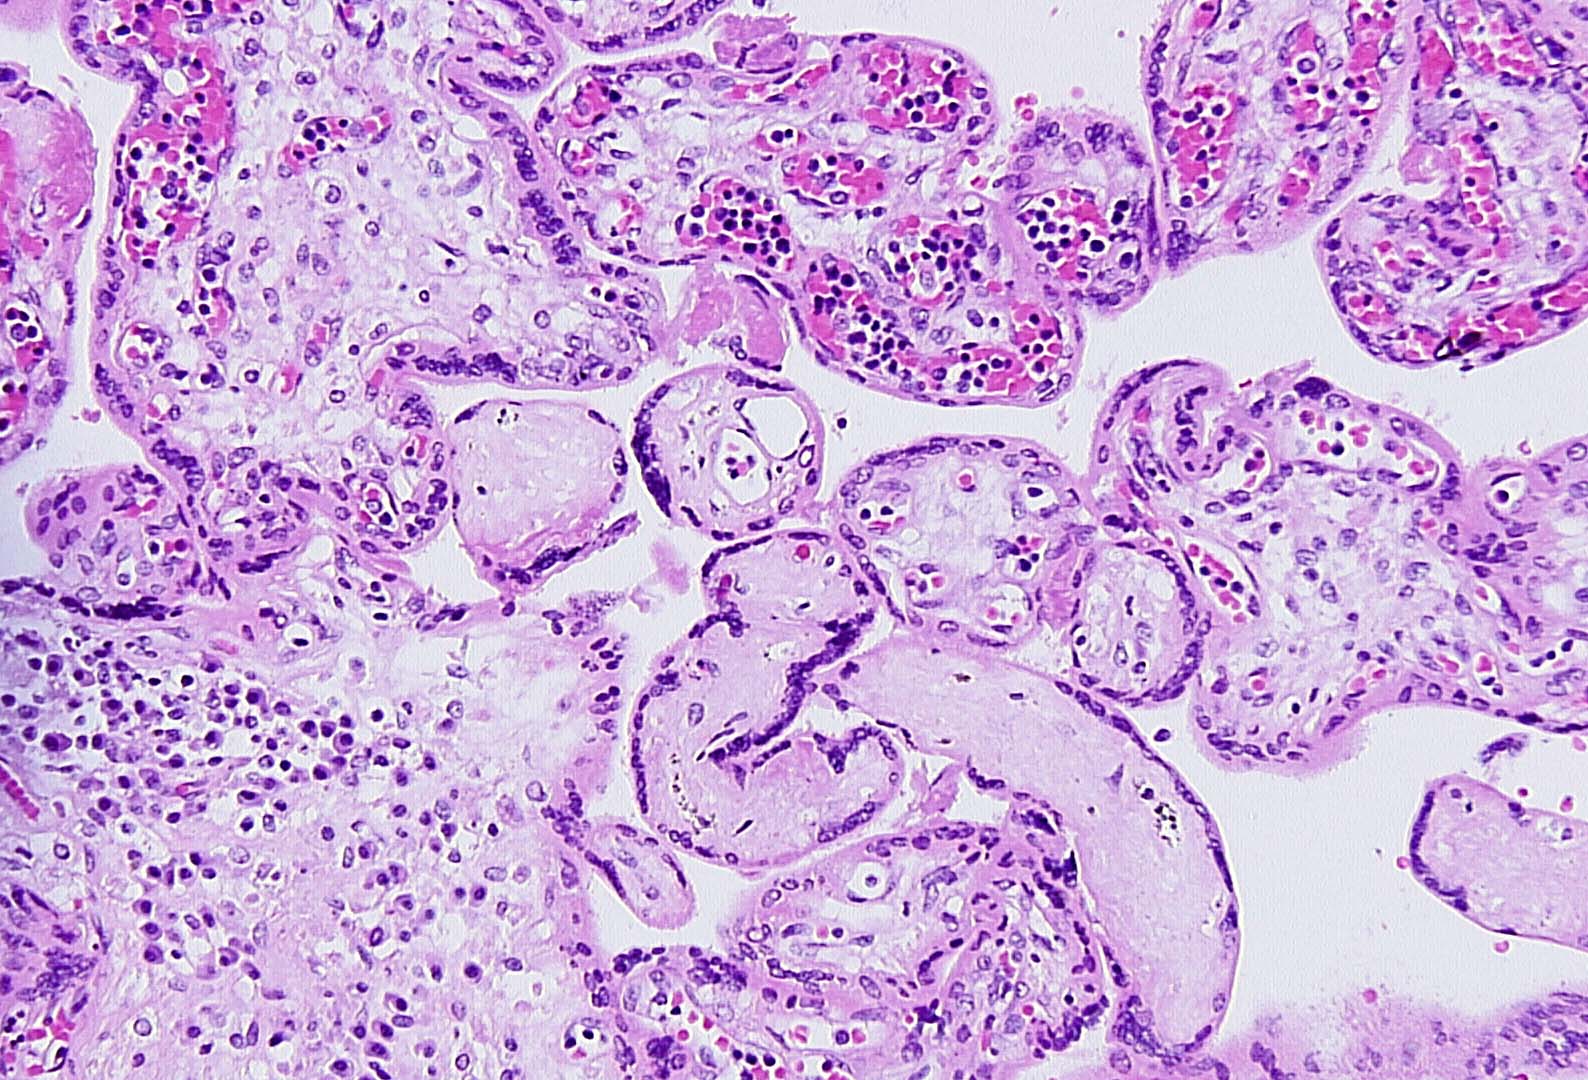

17-year-old primigravida with delivery of live born infant at 31 weeks...